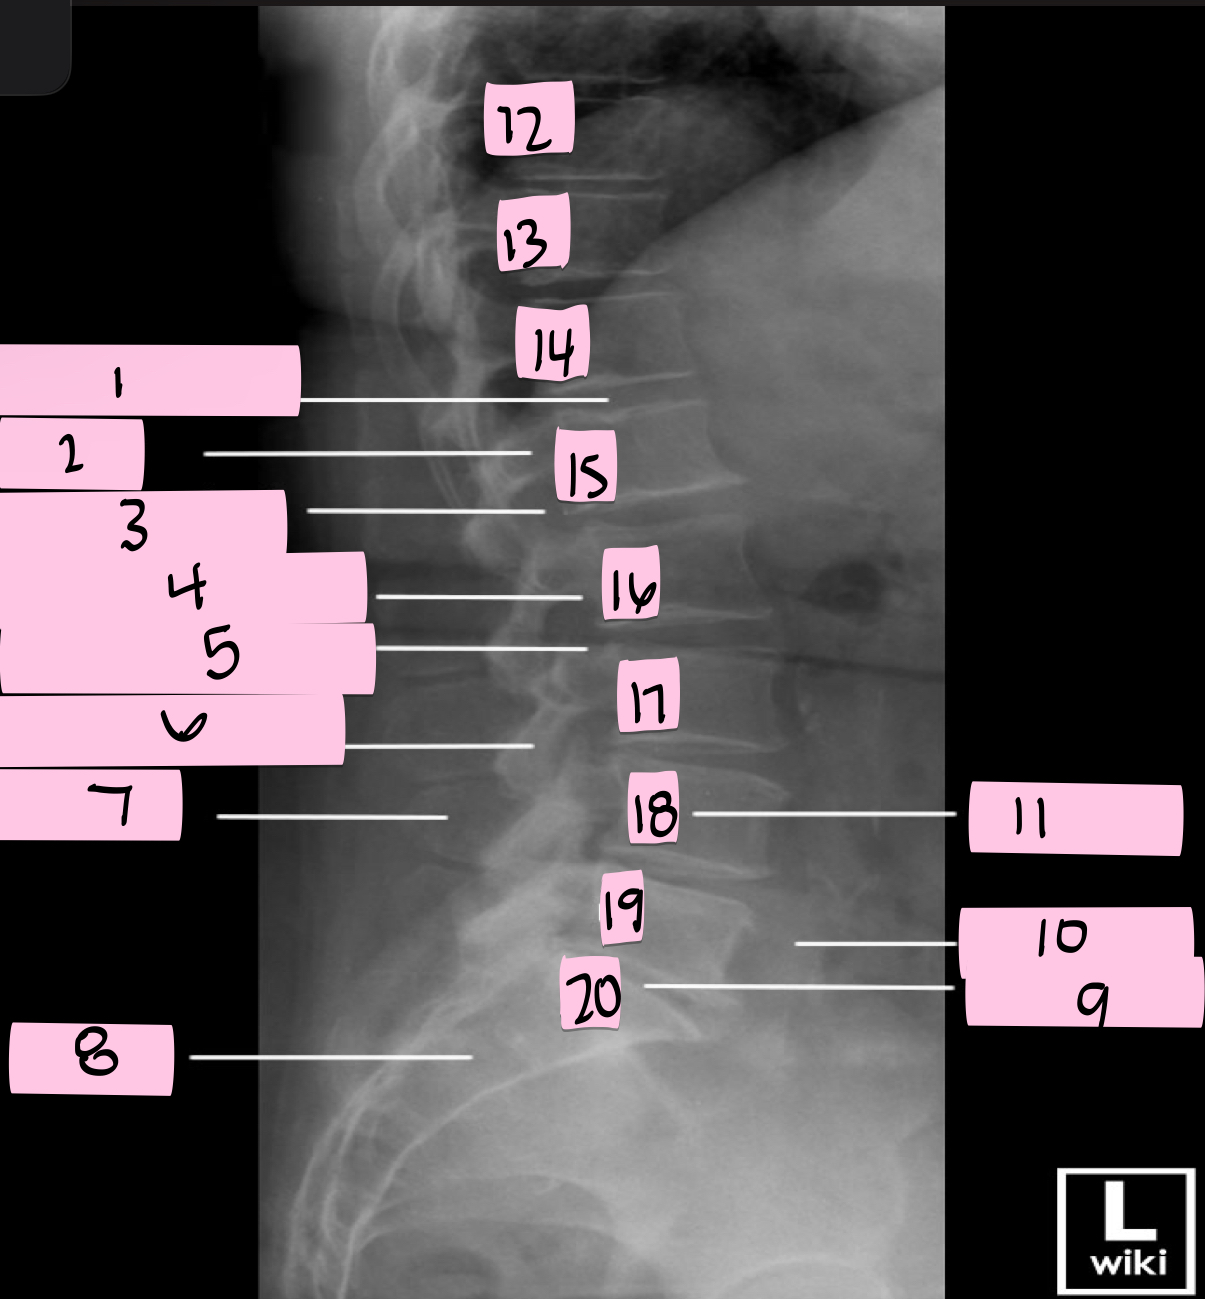

What is 1 pointing to?

Intervertebral disk

What is 2 pointing to?

Pedicle

What is 3 pointing to?

Intervertebral foramen

What is 4 pointing to?

Inferior vertebral notch

What is 5 pointing to?

Superior vertebral notch

What is 6 pointing to?

Inferior articular process

What is 7 pointing to?

Spinous process

What is 8 pointing to?

Sacrum

What is 9 pointing to?

L5 S1 joint

What is 10 pointing to?

Iliac crest

What is 11 pointing to?

Vertebral body (L4)

What is 12 pointing to?

T10

What is 13 pointing to?

T11

What is 14 pointing to?

T12

What is 15 pointing to?

L1

What is 16 pointing to?

L2

What is 17 pointing to?

L3

What is 18 pointing to?

L4

What is 19 pointing to?

L5

What is 20 pointing to?

S1